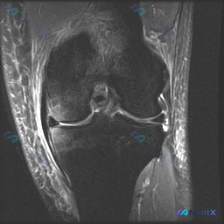

提问:单张膝关节冠状位MRI图像,问题是图像中可见的异常是什么,提示半月板异常。

先确认这张影像的基本信息:这是膝关节冠状位MRI,对比良好,骨髓信号正常,可以看到股骨远端、胫骨近端、内外侧关节间隙、半月板和侧副韧带结构,左侧为外侧结构、右侧为内侧结构。

- 骨骼软骨: 股骨髁、胫骨平台骨髓信号无异常,骨皮质连续,关节软骨厚度均匀,无剥脱变薄,关节边缘无明显骨赘,退行性变不显著

- 半月板: 内外侧半月板体部均呈正常低信号三角形影,信号均匀,形态规整,未见明显撕裂信号

- 韧带: 内外侧副韧带走行自然,信号均匀,无水肿增粗;冠状位可见部分交叉韧带,走行连续,无明显异常

- 软组织与关节: 周围软组织信号均匀,无肿块或肿胀,关节腔内无明显异常积液,也没有骨质破坏、病理性肿块等严重病变的红旗征象

针对提问的「半月板异常」,基于这张单层面图像的直接结论是:未见明确半月板撕裂或形态学异常,但必须说明:MRI对半月板的全面评估依赖多序列、多平面图像,单张冠状位可能无法显示特定类型或位于前后角的撕裂,不能完全排除隐匿性病变。